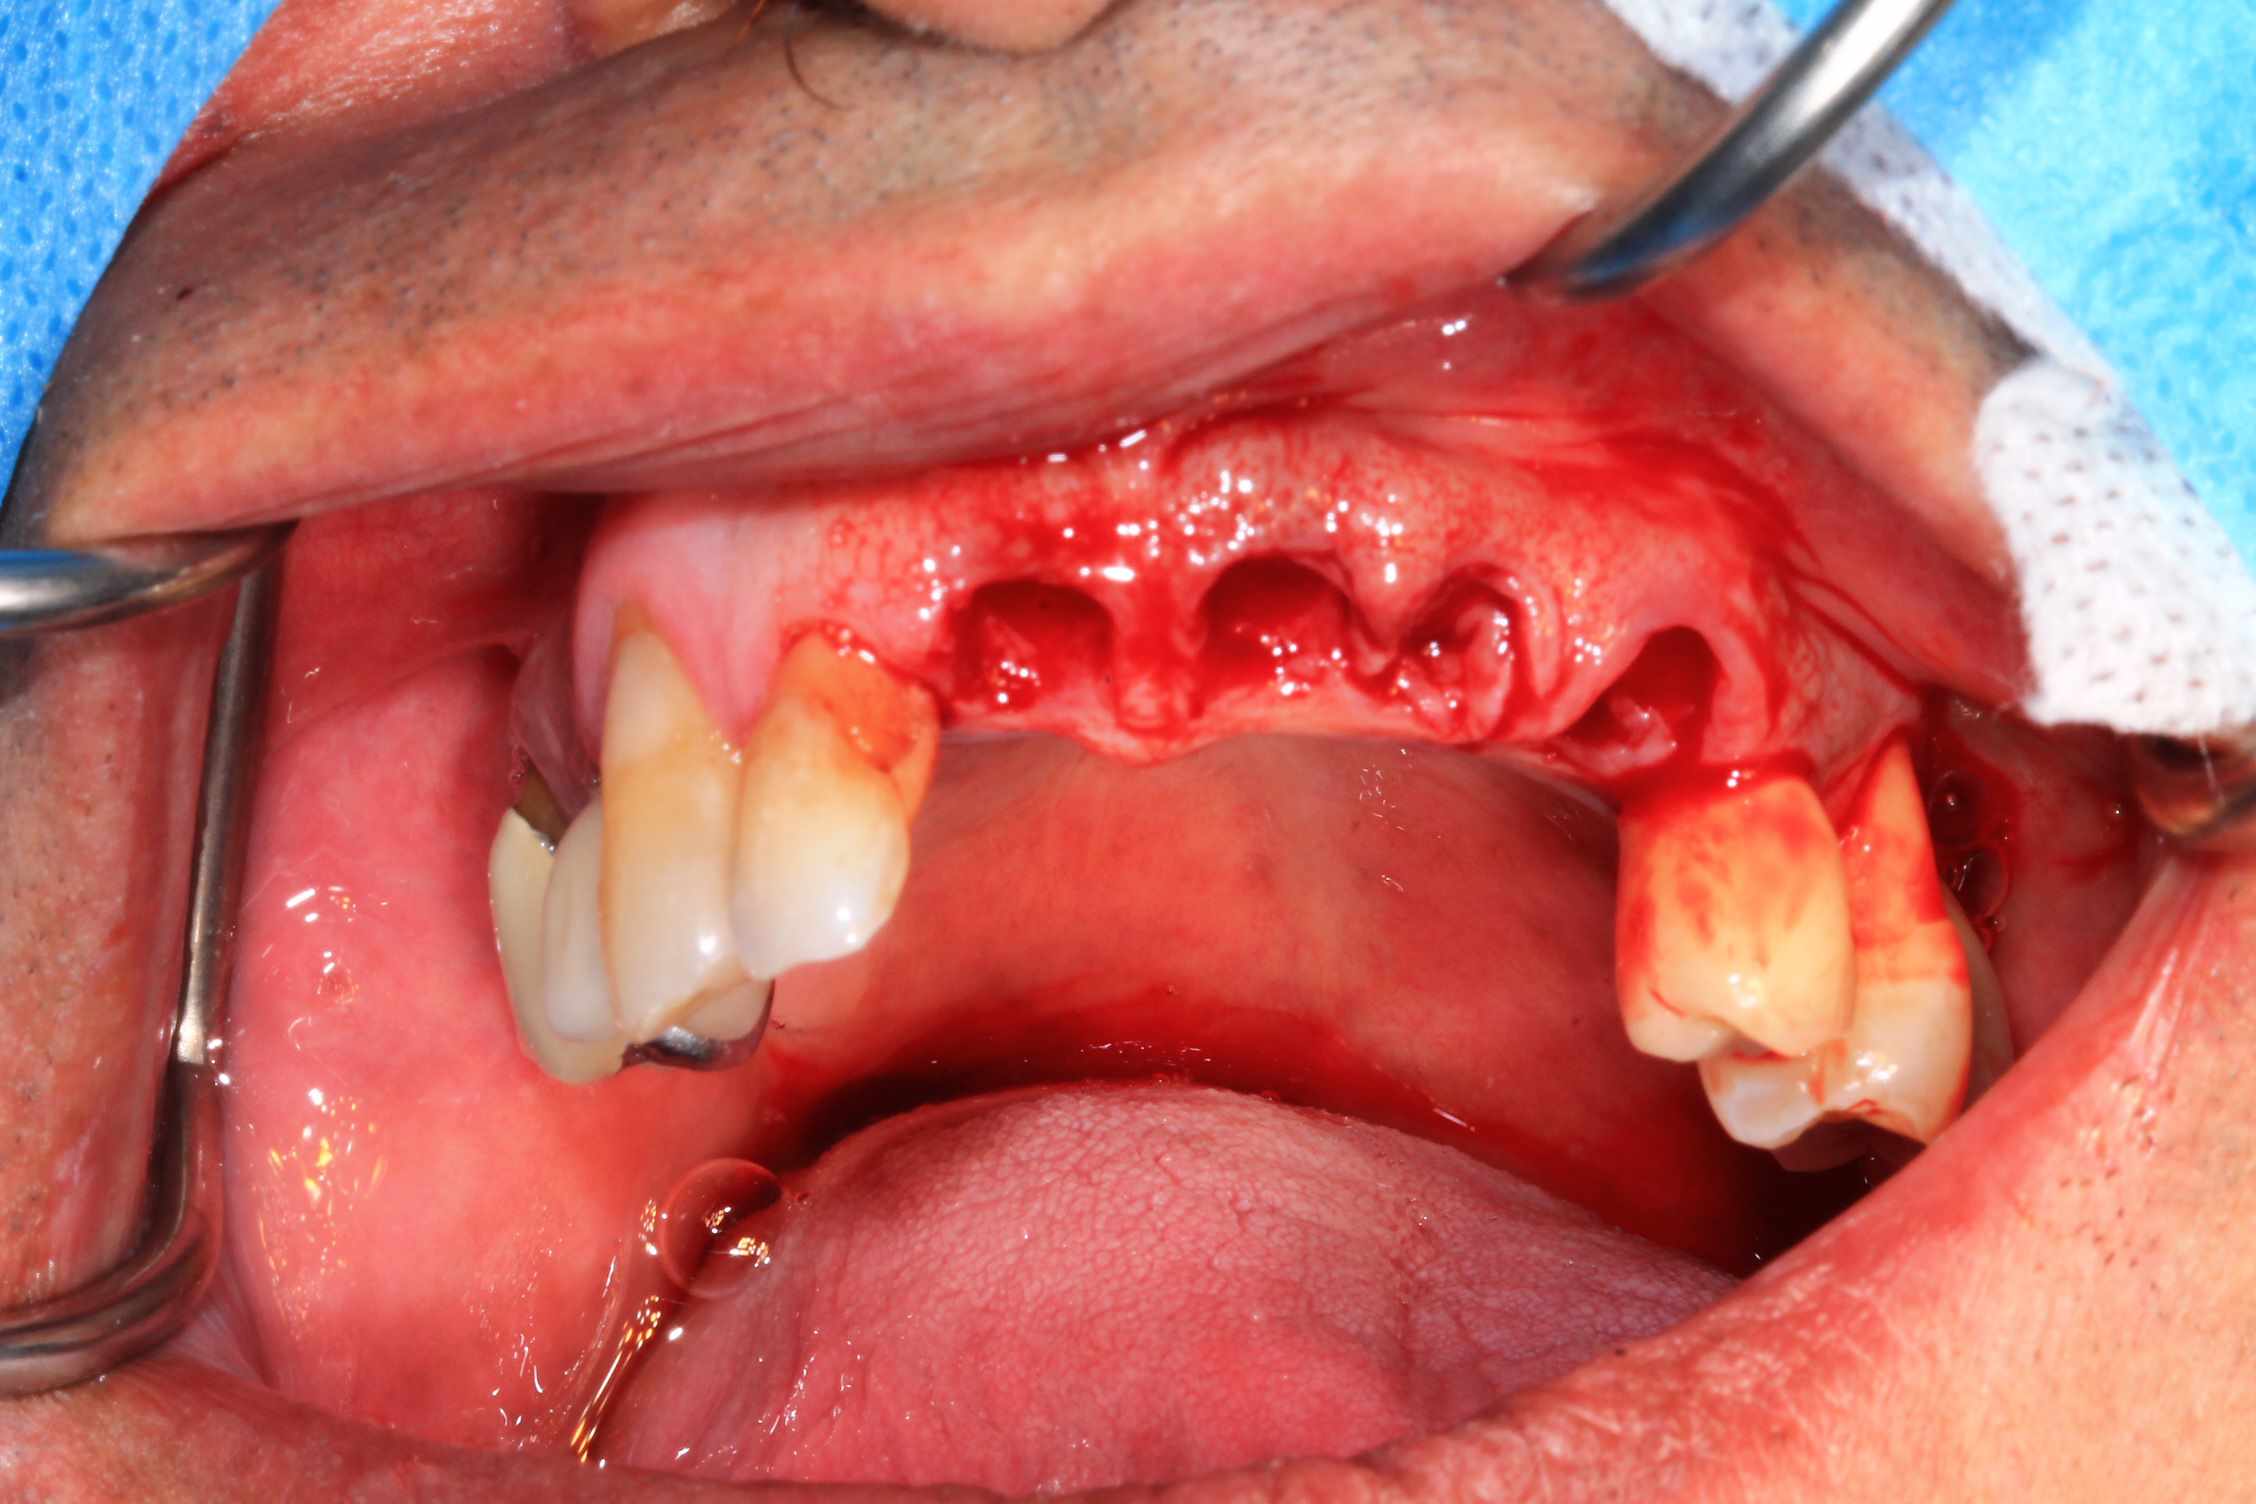

Chir le vendredi matin. au vu de la possibilité de reculer pas mal les implants postérieurs, je trouvais qu'il y avait trop de porté entre les implants : je pars donc sur 6 implants.

Mais malgré les gros renforts, le guide résine n'est pas assez rigide : impossible de poser le bridge en immédiat. obligé de fraiser le bridge ( j'aurais du en prévoir un autre évidé, ce que je prévois pour lundi prochain ) et de mettre des piliers provisoires : 40 m de travail de labo en plus..

Mais un chouette résultat.